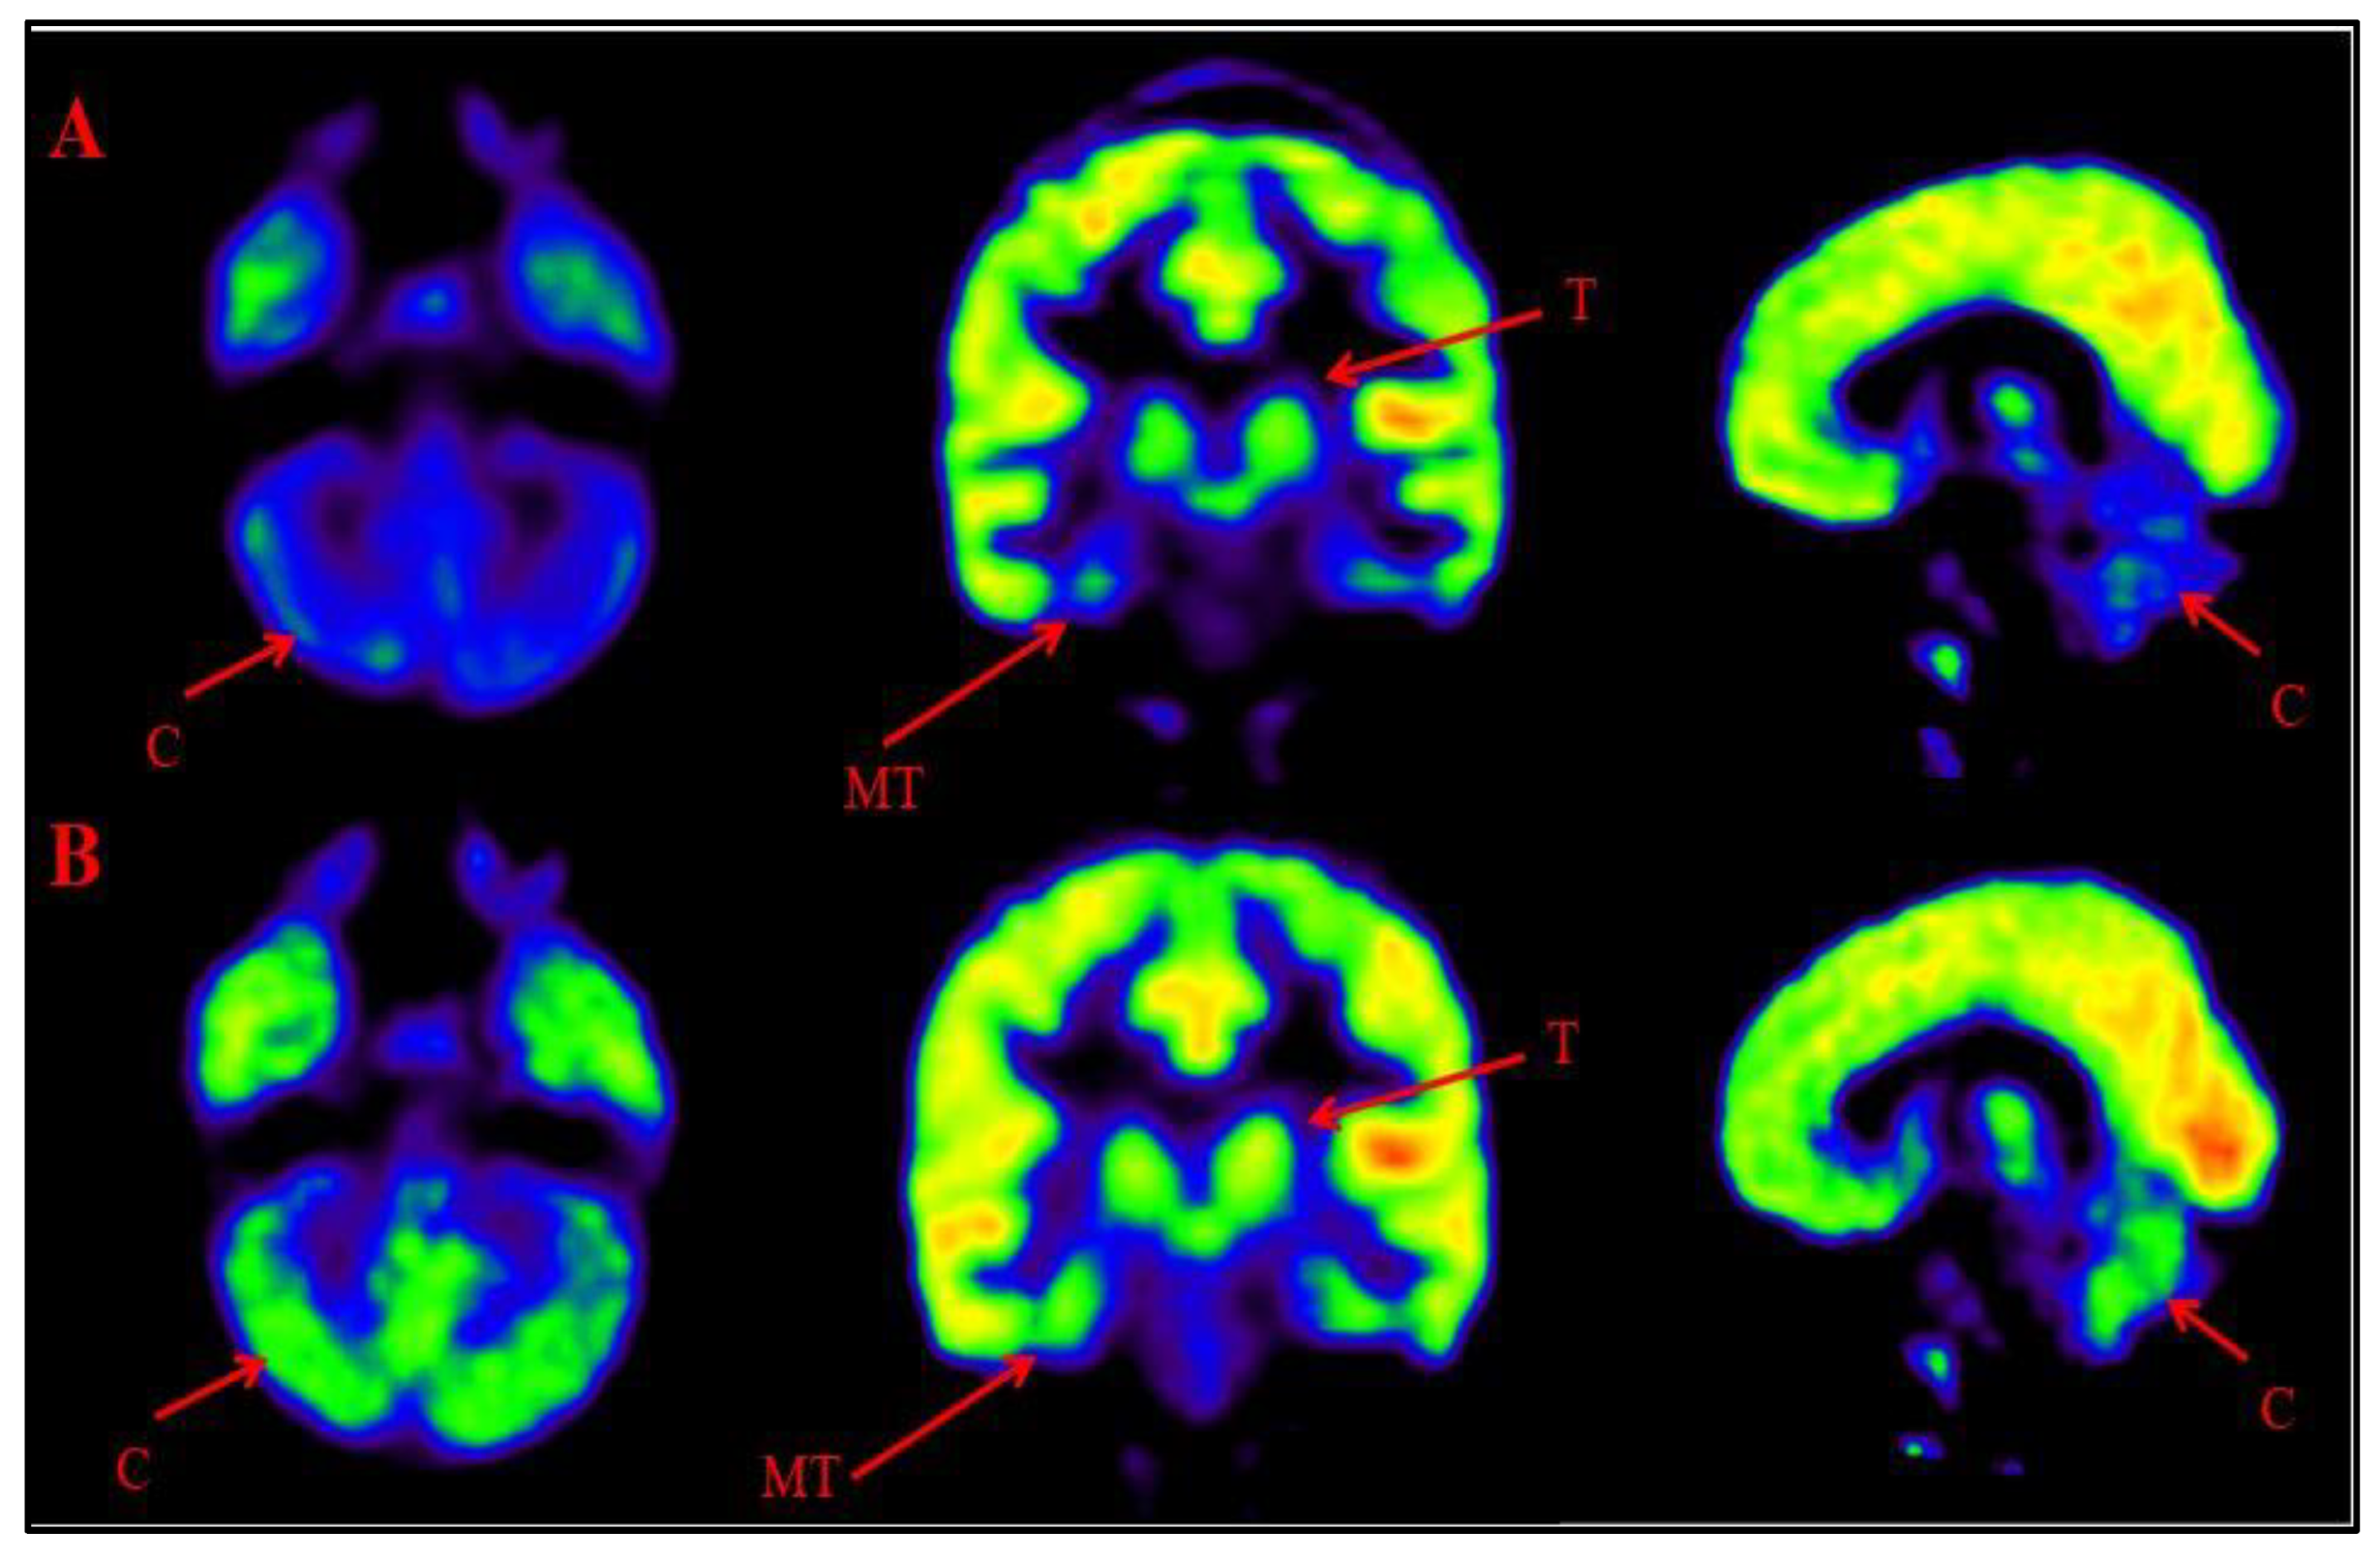

Comparison of Brain FDG PET scans performed before and after intervention was done to observe the metabolic changes in the brain after BMMNCs administration. 18-FDG PET scan shows glucose uptake in different brain areas and also depicts efficacy of treatment in ASD patients via change in metabolic rate [16]. A comparative PET CT scan was performed in 401 patients. Improved metabolism, reduction in percent hypometabolism, was observed in brain regions including amygdala, hippocampus, parahippocampal gyrus, caudate nucleus, cerebellum, mesial temporal lobe, thalamus, superior and middle temporal poles (Figure 6, Figure 7). The grading of these distinct nine regions showed statistically significant improvement on Wilcoxon’s signed rank test (p<0.05) after cell therapy.

Figure 6. Representative images of Comparative Brain FDG PET scan of ASD patients performed before and after Cell therapy. Figure 6A: Top Row (a): Arrow marked blue areas represent hypometabolism. Bottom Row (B): Arrow marked green areas showing improved metabolism post Cell therapy. Cerebellum (C), Medial temporal cortex (MT) and Thalamus (T).